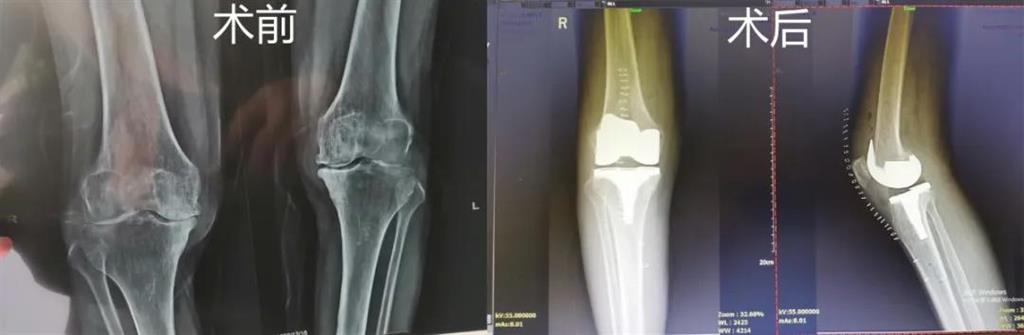

和平國(guó)際醫(yī)院副院長(zhǎng)、骨科中心主任劉丹在診斷后發(fā)現(xiàn),老人雙側(cè)膝關(guān)節(jié)患有骨性關(guān)節(jié)炎,右側(cè)膝關(guān)節(jié)較為嚴(yán)重,而且關(guān)節(jié)磨損嚴(yán)重關(guān)節(jié)間隙基本消失

經(jīng)過(guò)進(jìn)一步檢查后,劉丹帶領(lǐng)團(tuán)隊(duì)在計(jì)算機(jī)導(dǎo)航系統(tǒng)的輔助下,為老人實(shí)施了右側(cè)全膝關(guān)節(jié)置換手術(shù)。術(shù)中出血明顯減少,術(shù)后疼痛腫脹等反應(yīng)輕微畸形矯正力線恢復(fù)理想,而且功能恢復(fù)快速,術(shù)后四天就可以下地行走。